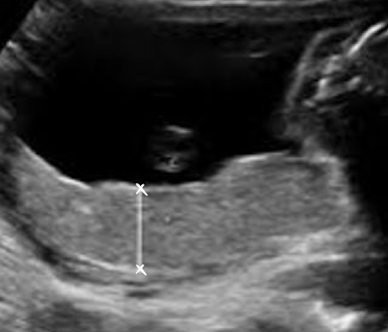

measuring technique for placenta

measure in AP dimension

thickest portion perpendicular to uterine wall

DO NOT include uterine wall in measurement

typically measure after 23 weeks